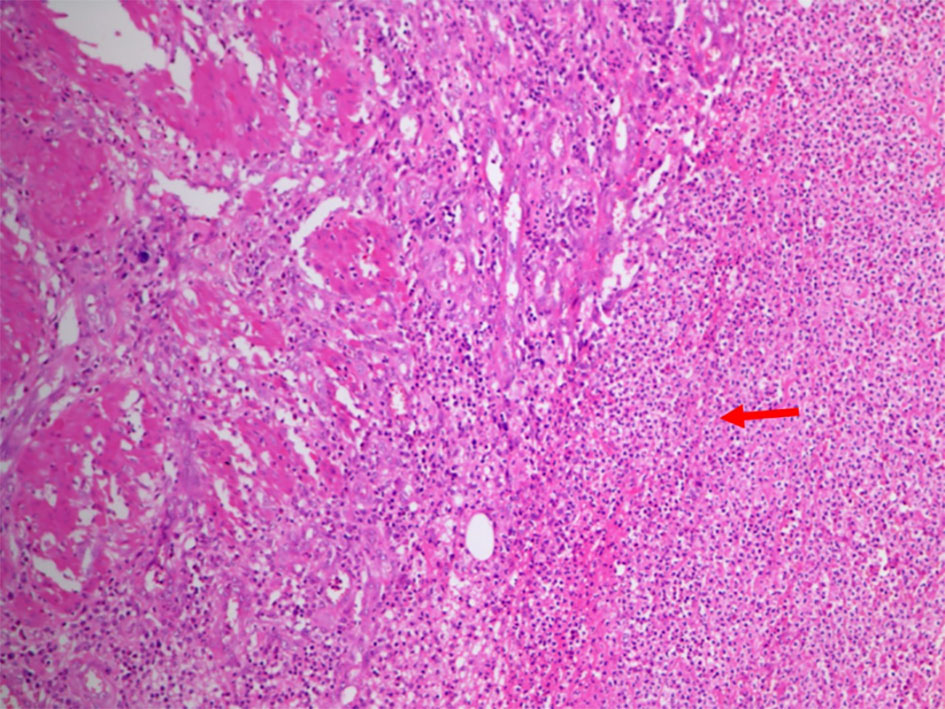

Based on the history, clinical examination and investigations done, probable malignant urachal lesion with co-existing urinary tract infection was considered. Excision of the urachal mass was planned. Lymph node dissection was planned to be done after frozen section. A midline infraumbilical incision with 3 cm supraumbilical extension was made. Mass was excised in toto with about 1 cm of cuff of urinary bladder (Fig. 3a-c). Frozen section suggested an inflammatory cystic mass with abscess formation. Final histopathology revealed urachal cyst abscess. Gross cut section showed pus in the center of the lesion. Microscopically, there was dense polymorphic inflammatory infiltrate in the cyst wall and in the bladder mucosa (Fig. 4). Cyst wall was lined by vascular granulation tissue. No parasitic/fungal elements were found. Adjoining bladder mucosa showed reactive urothelial hyperplasia with focal erosions and surrounding omentum shoed acute inflammation with fat necrosis.

![]() Click for large image | Figure 4. Photomicrograph showed dense polymorphic inflammatory infiltrate (arrow) in the cyst wall and also in the central area of bladder mucosa. The cyst wall showed lining made up of vascular granulation tissue. |